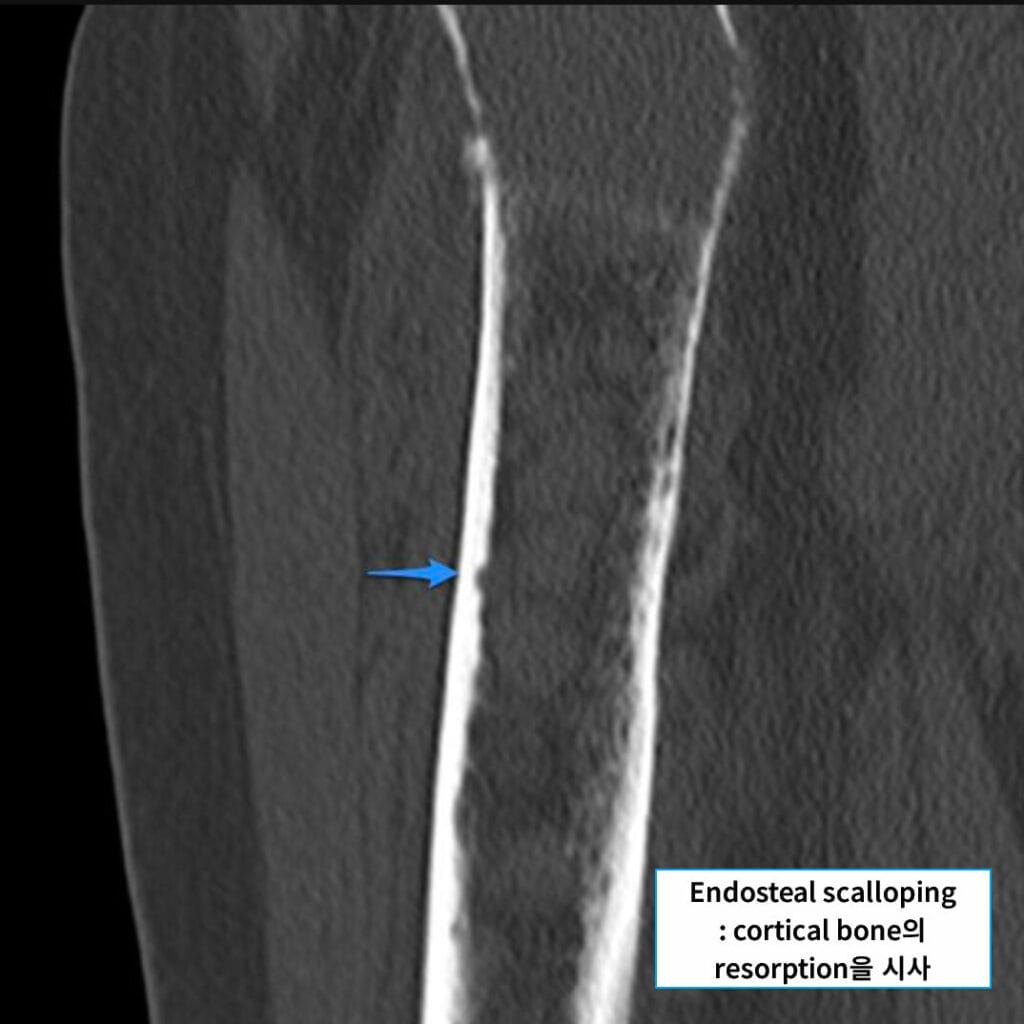

Dixon A, Endosteal scalloping in myeloma. Case study, Radiopaedia.org (Accessed on 22 Jul 2025) https://doi.org/10.53347/rID-9472

CT 소견

🟦 골소실 및 골파괴 병변

X-ray에서 보이지 않던 작은 병변도 확인할 수 있으며, cortical disruption이나 골절을 평가하는 데 유용합니다.

🟦 Soft tissue mass 동반 가능

종양세포의 연부조직 침윤으로 종괴가 형성될 수 있습니다.

Gaillard F, Multiple myeloma – femur. Case study, Radiopaedia.org (Accessed on 22 Jul 2025) https://doi.org/10.53347/rID-16464